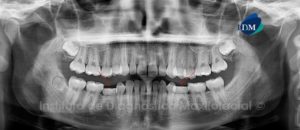

Paciente masculino de 18 años de edad que es referido para descartar las ausencias de las piezas 35 y 45; así como para la evaluación